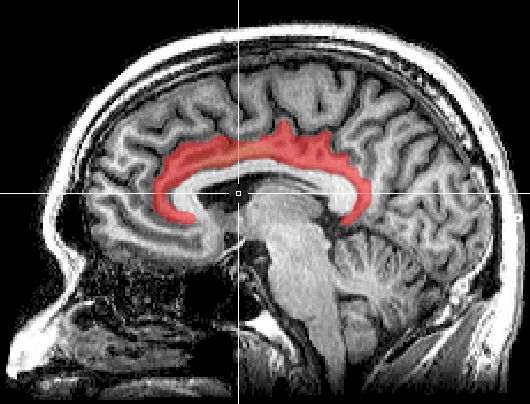

When they looked at the jilted monkey’s brain, two areas in particular lit up.

An MRI and blood draw afterward gave Maninger and Bales a peek at the animal’s brain, and in addition to higher testosterone and stress hormones, two more areas deep within his brain were triggered. The first, the cingulate cortex, has a lot to do with social rejection. The second, the lateral septum, is connected to bonding.

Put together, these areas of the brain appear to show us what Victorian novels, romantic comedies, and reality TV shows have long suspected: Jealousy is intimately tied to monogamy.